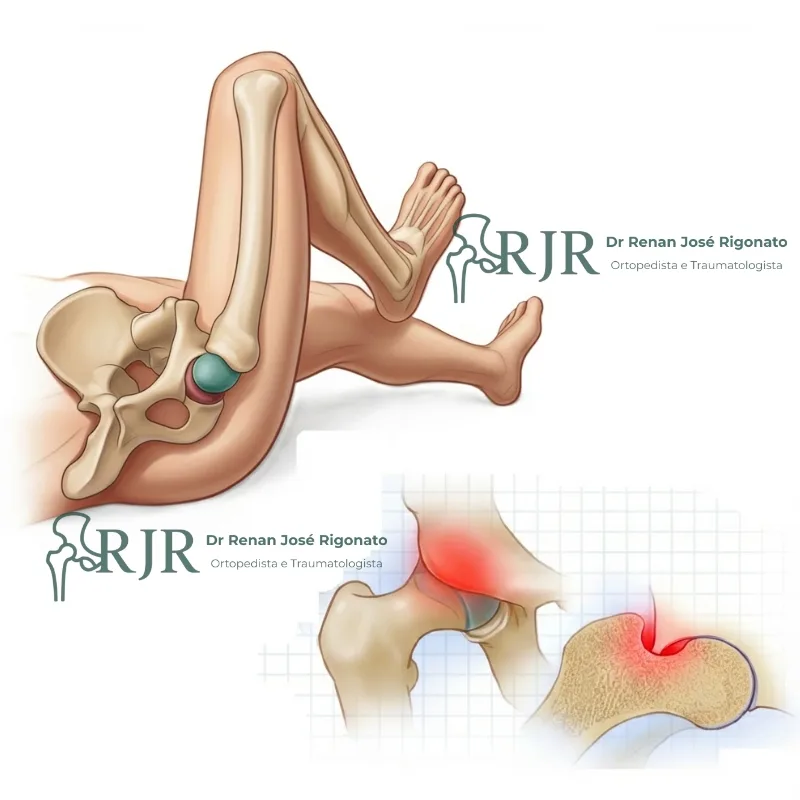

Impacto femoroacetabular

Frequente causa de dor em jovens e adultos ativos. O tratamento precoce evita lesões na cartilagem e preserva a articulação.

Osteonecrose do fêmur

Condição que compromete a mobilidade do quadril pela falta de circulação. O diagnóstico precoce preserva a articulação.